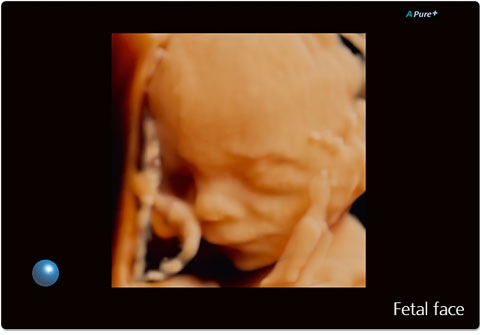

Режимы визуализации Canon (Toshiba) Aplio 300

B, M, PWD, CWD, ЦДК, THI, 4D, динамический поток (Dynamic Flow), энергетический доплер (Power), контрастная эхография (CHI 2D) и комбинированные режимы, включая следующие: B/M, B/PWD, BDF/PDW, BDF/MDF,BDF/MDF/PWD, 2D/CWD, BDF/CWD (BDF-режим изображения, в котором CFM изображение накладывается на B-режим изображения, MDF-режим изображения, в котором CFM изображение накладывается на M-режим изображения)

• STIC - исследование сердца плода в режиме объёмной визуализации

• STIC Color - цветная объёмная визуализация сердца плода

• Трехмерная эхография в реальном времени с использованием специализированных 4D датчиков;

• Программа анализа сердца плода в трех проекциях в реальном времени 4D Stick;